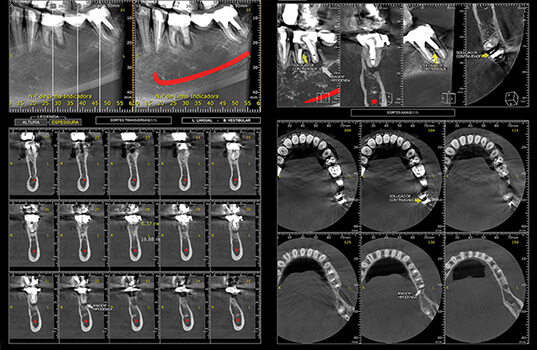

A Tomografia Computadorizada Cone Beam é uma radiografia 3D que é bastante usada na odontologia para ter uma visão detalhada dos ossos da boca, mandíbula e maxila. Ela é muito útil para descobrir problemas como fraturas, tumores, cistos, infecções e outros problemas dentários. Além disso, a Tomografia Computadorizada Cone Beam também é usada para planejar cirurgias na boca, como a colocação de implantes dentários, como também para avaliar o desenvolvimento de tratamentos.

Na Tomografia Computadorizada Cone Beam, o paciente é posicionado na máquina de Raio-X, que gira ao redor da cabeça para fazer uma série de imagens 3D. Em seguida, um profissional especializado utilizando um software junta as imagens para formar uma visão detalhada das estruturas ósseas da boca.

Em resumo, a Tomografia Computadorizada Cone Beam é uma ferramenta valiosa na odontologia, no qual permite aos dentistas terem uma visão detalhada das estruturas ósseas da boca para diagnosticar e tratar problemas de saúde.